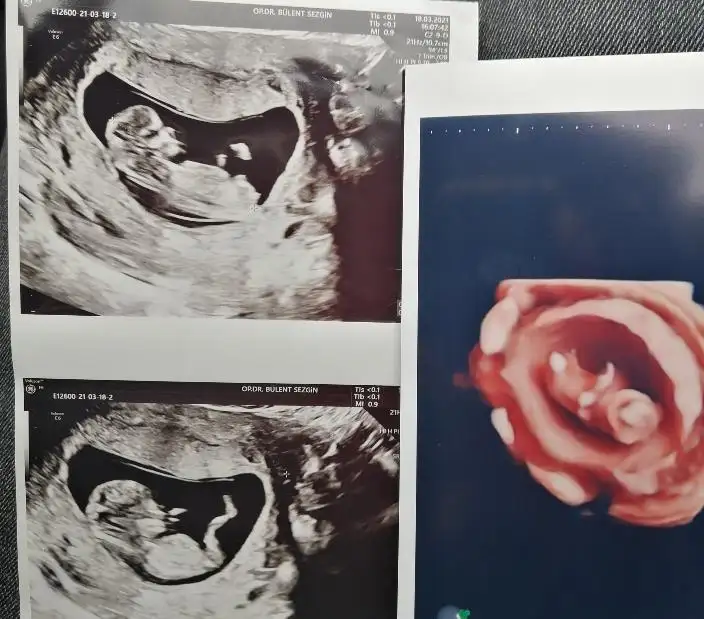

Evet burada kıza benziyo bu arada kafa yapısı benimkinin kafasına çok benziyor ilk fotoda bak atıyorum sana. Alın daha düz olunca kız olurmuş skull teorisine görekuzu bakk kizimin 12+4 fotolarini ekledim, nub vs diyon ya uyuyor muburadan teorileri destekleyip curutebiliriz lakin kiz olarak dogdu

7 haftalık var mı keseye konuma göre ramzi teorisinde de bakalım hahahkuzu bakk kizimin 12+4 fotolarini ekledim, nub vs diyon ya uyuyor muburadan teorileri destekleyip curutebiliriz lakin kiz olarak dogdu

Bak bir de bunu buldum, cok belirsiz ama belki fikir verir, daha kucukmus ama ne kdrlik blmyrm yazmiyoAyyy evet yaa yurt dışında öyleymiş ilk duyduğumda çok şaşırmıştım şükür valla ülkemize en az ayda 1 görülüyor